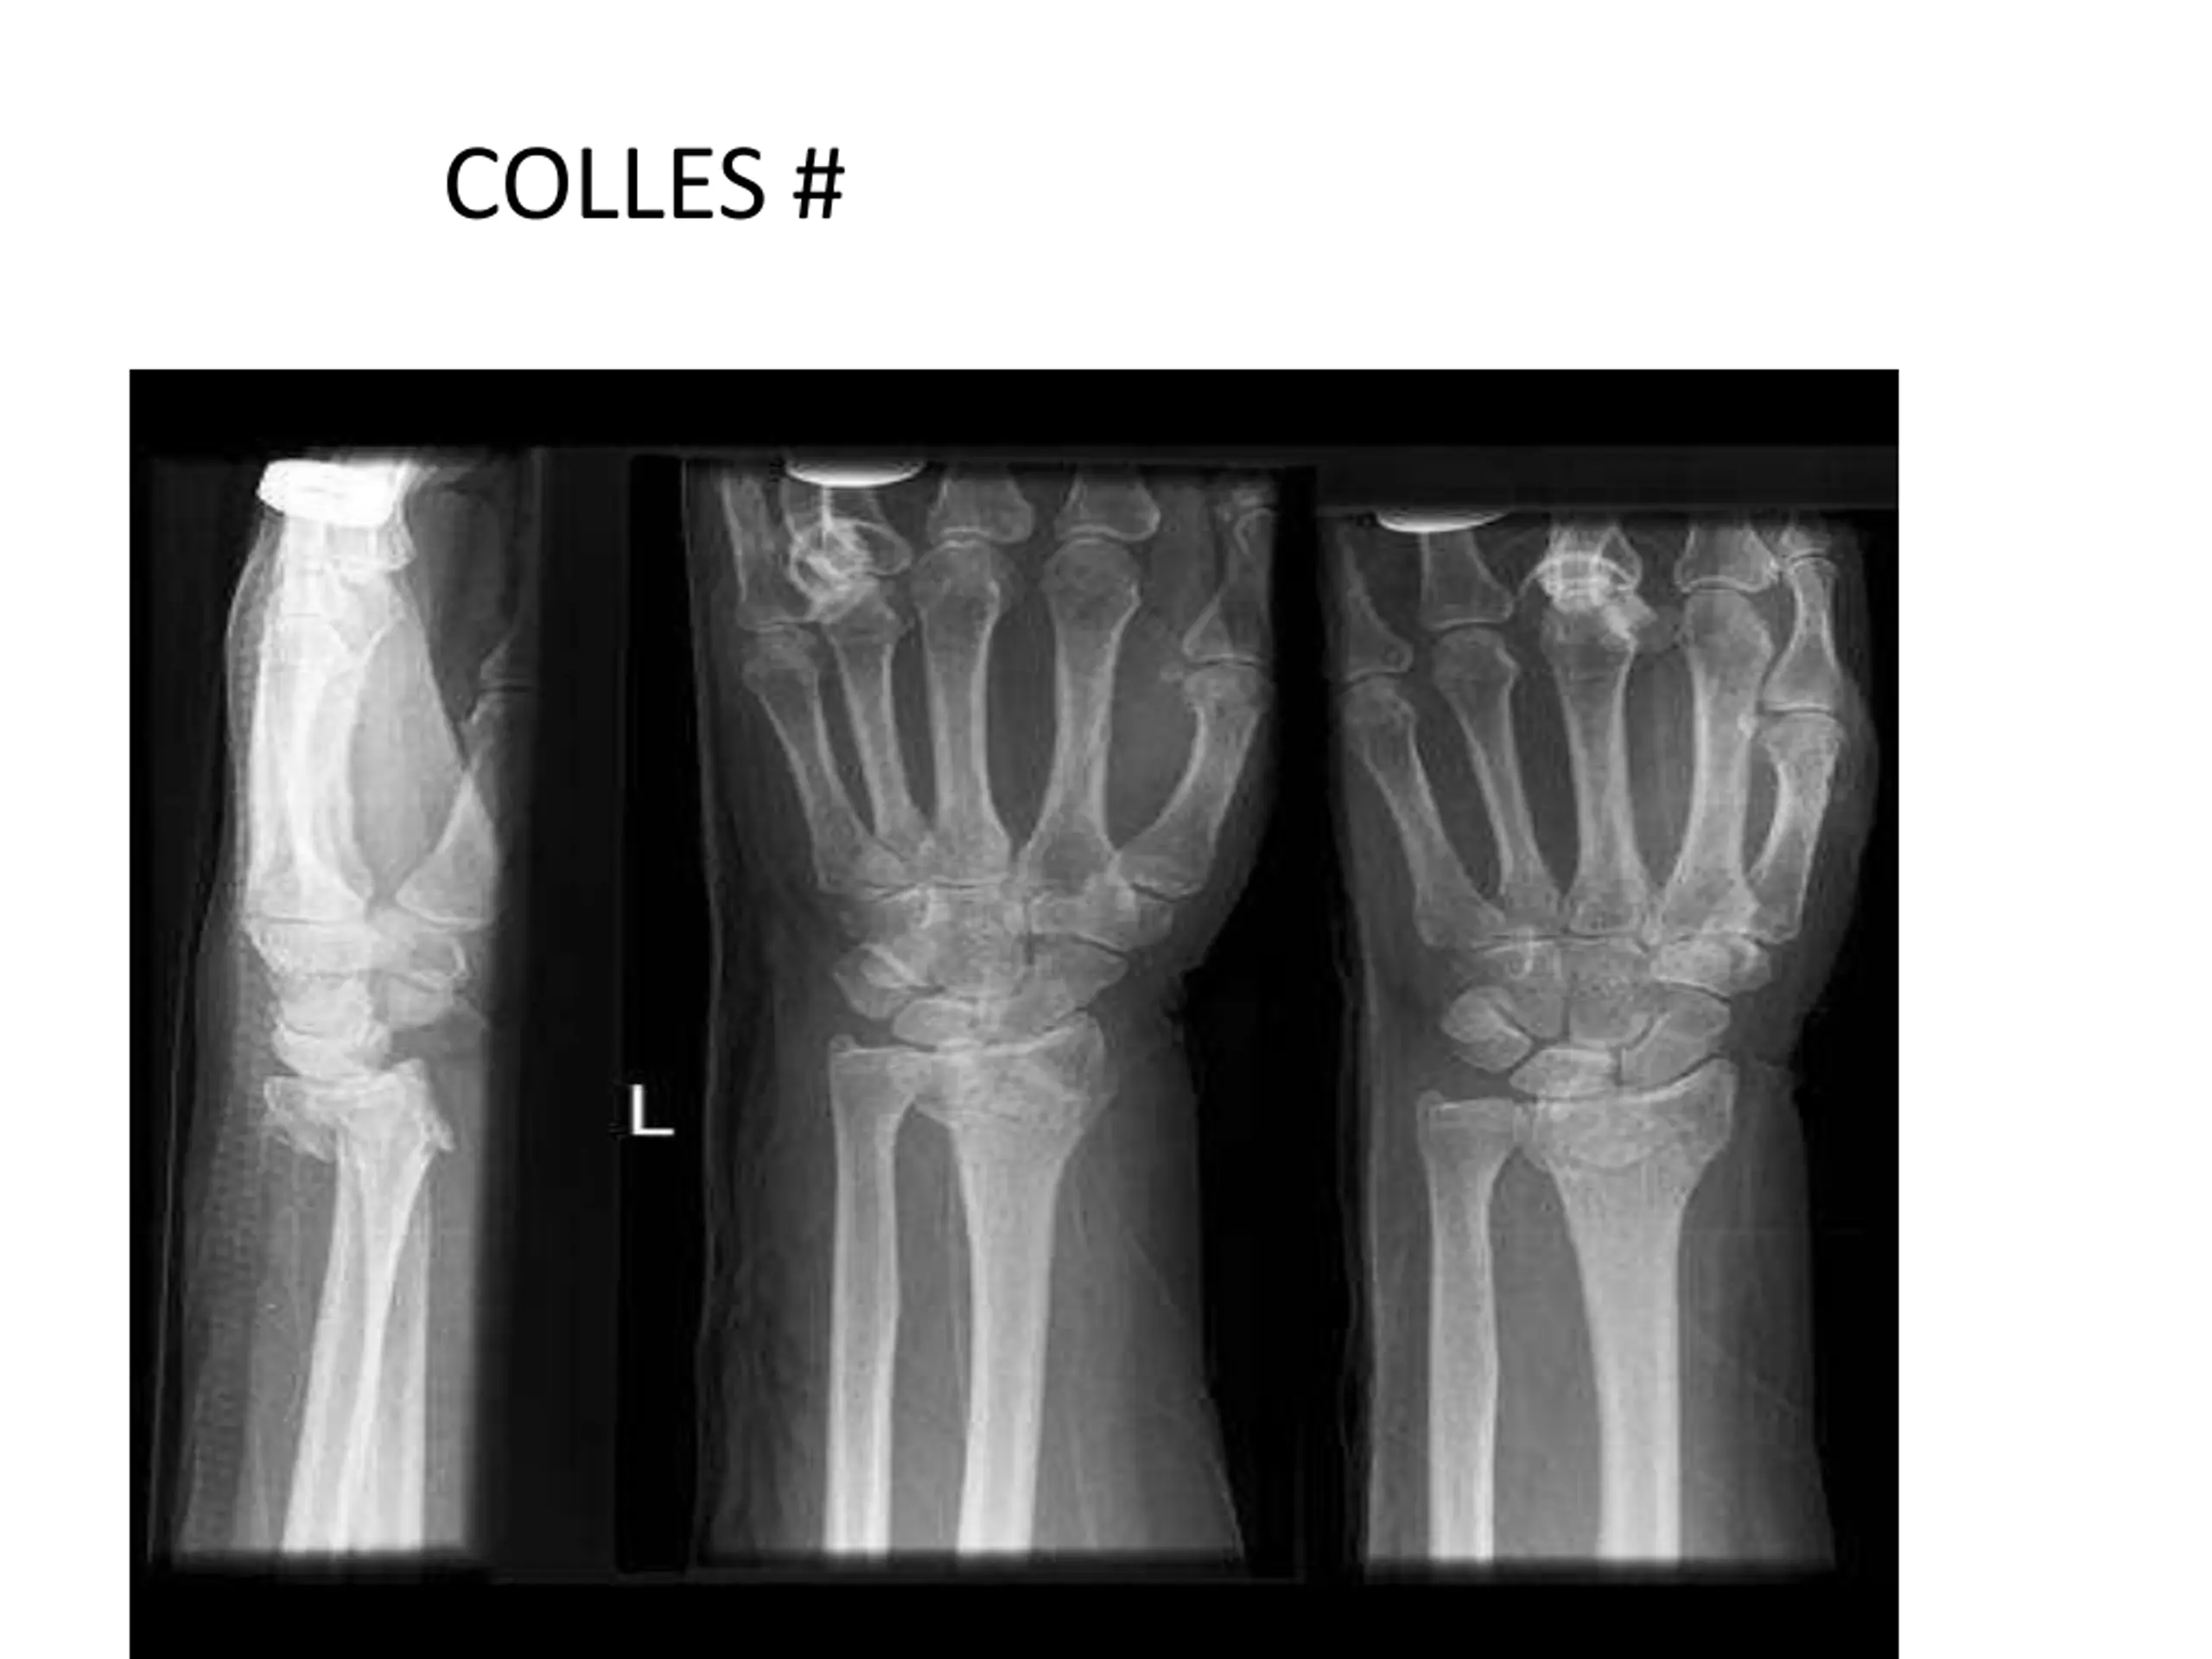

7. COLLES #

5. ORTHOPAEDIC CONDITIONS IN INPATIENTS UPPER LIMB SUPRA CONDYLAR # HUMERUS BOTH BONE # FORE ARM COLLES #